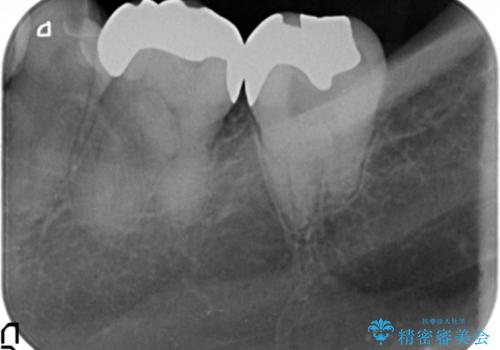

- 12万円 ゴールドインレー×2費用は治療当時の料金となります

ゴールドインレーについて

ゴールドは見た目に難がありますが、歯を削る量がセラミックに比べて少ない・複雑な形にも追従しやすい・壊れにくいなどの利点があります。

PGA(ゴールド)クラウン、インレーの注意事項(リスク・副作用など)

- インレーおよびクラウンは脱離するリスクがあります

- 形成量はセラミックより少ないですが、歯の形成、修復後に歯に症状が出ることがあります